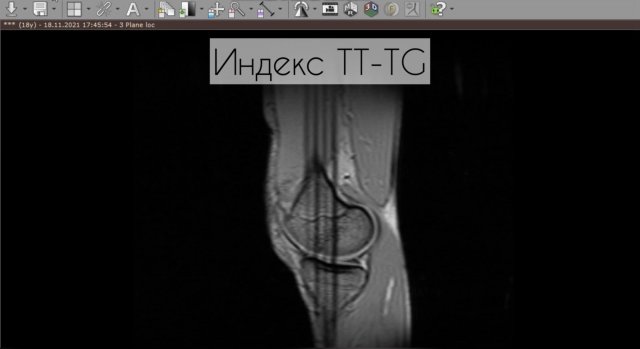

Индекс TT-TG по МРТ

369 просмотров